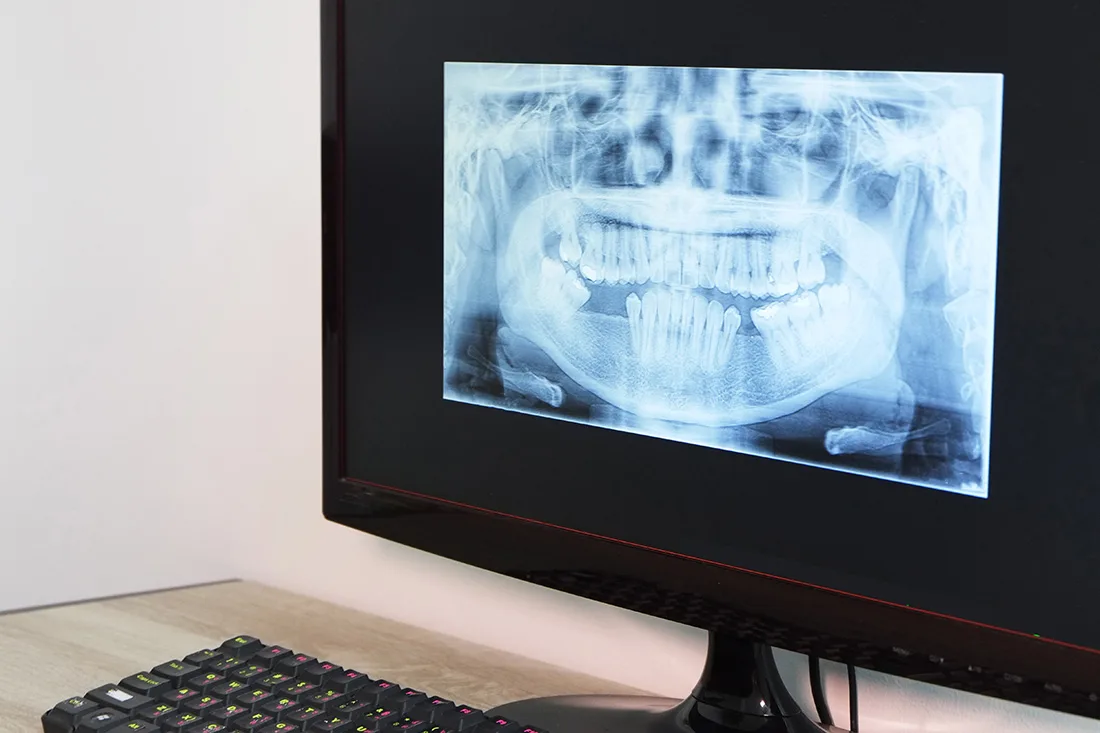

Digital X-Rays

Digital x-rays are safe, quick, and comfortable. Using the latest technology, we can create crisp, high-resolution images of your mouth’s structure, so we can make accurate diagnoses and treatment plans. Digital x-rays use only a fraction of the radiation as traditional film x-rays, so you can rest easy. Most patients receive one or two full sets of x-rays every year, but we may recommend additional imaging in the case of a dental emergency, or if we find an oral health issue that we need to investigate further.